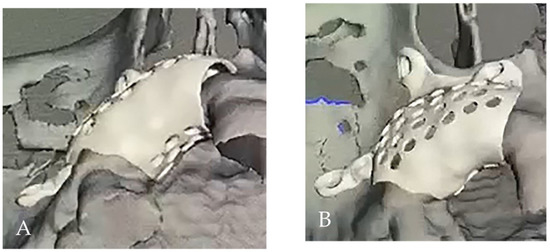

Customized 3D-Printed Titanium Mesh Developed for an Aesthetic Zone to Regenerate a Complex Bone Defect Resulting after a Deficient Odontectomy: A Case Report

Background and Objectives: Alveolar ridge augmentation in the complex bone defect is a popular topic in implantology. Guided bone regeneration (GBR) is one of the most commonly applied methods to reconstruct alveolar bone. The application of a membrane is the fundamental principle of GBR. There are many membrane types used in oral surgery, but the advantage of the titanium mesh is the rigidity which provides space maintenance and prevents contour collapse. The smooth surface also reduces bacterial contamination. Using computer-aided design (CAD) and computer-aided manufacturing (CAM) in dentistry allows us to obtain the perfect architecture form of the mesh, which covers and protects the bone reconstruction. Case presentation: We present a surgical case of a 27-year-old female patient with severe aesthetic bone atrophy after a deficient odontectomy. Based on the GBR clinical applications, the technique consists of bone reconstruction and a customized titanium mesh application. Using mesh titanium in this case presentation was a reliable alternative to perform a lateral alveolar bone augmentation and reconstruct ridge deformities before reaching an ideal implant placement. Conclusions: According to our case report, the customized titanium mesh could be a valuable option for guided bone regeneration in aesthetic maxillary defects. Full article